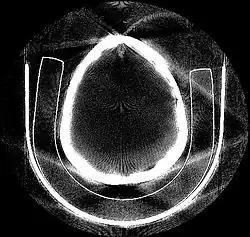

Tomographic reconstruction is a type of multidimensional inverse problem where the challenge is to yield an estimate of a specific system from a finite number of projections. The mathematical basis for tomographic imaging was laid down by Johann Radon. A notable example of applications is the reconstruction of computed tomography (CT) where cross-sectional images of patients are obtained in non-invasive manner. Recent developments have seen the Radon transform and its inverse used for tasks related to realistic object insertion required for testing and evaluating computed tomography use in airport security.[1]

This article applies in general to reconstruction methods for all kinds of tomography, but some of the terms and physical descriptions refer directly to the reconstruction of X-ray computed tomography.